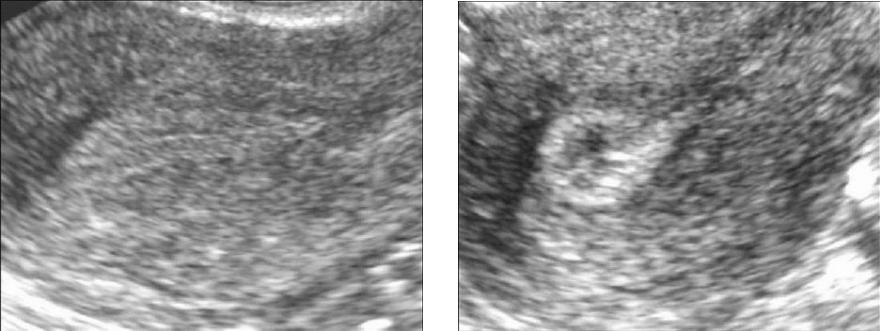

При проведении ультразвукового исследования (УЗИ) можно заметить признаки гиперплазии, которая проявляется в виде небольших участков размером от 2 до 7 мм, распределенных по всей поверхности эндометрия. Эти участки имеют неправильную форму и четкие контуры. В такой ситуации признаки эхогенности остаются стабильными на протяжении всего менструального цикла.

Эгиперэхогенность эндометрия выявляется во время ультразвукового обследования с использованием трансвагинального или трансабдоминального датчика. При этом равномерное увеличение эхогенности по всему эндометрию считается нормальным для определенных фаз менструального цикла. Однако случаи, обсуждаемые в данной статье, обладают другими визуальными признаками. Это проявляется в виде светлых участков с повышенной эхогенностью на фоне более или менее нормального эндометрия.